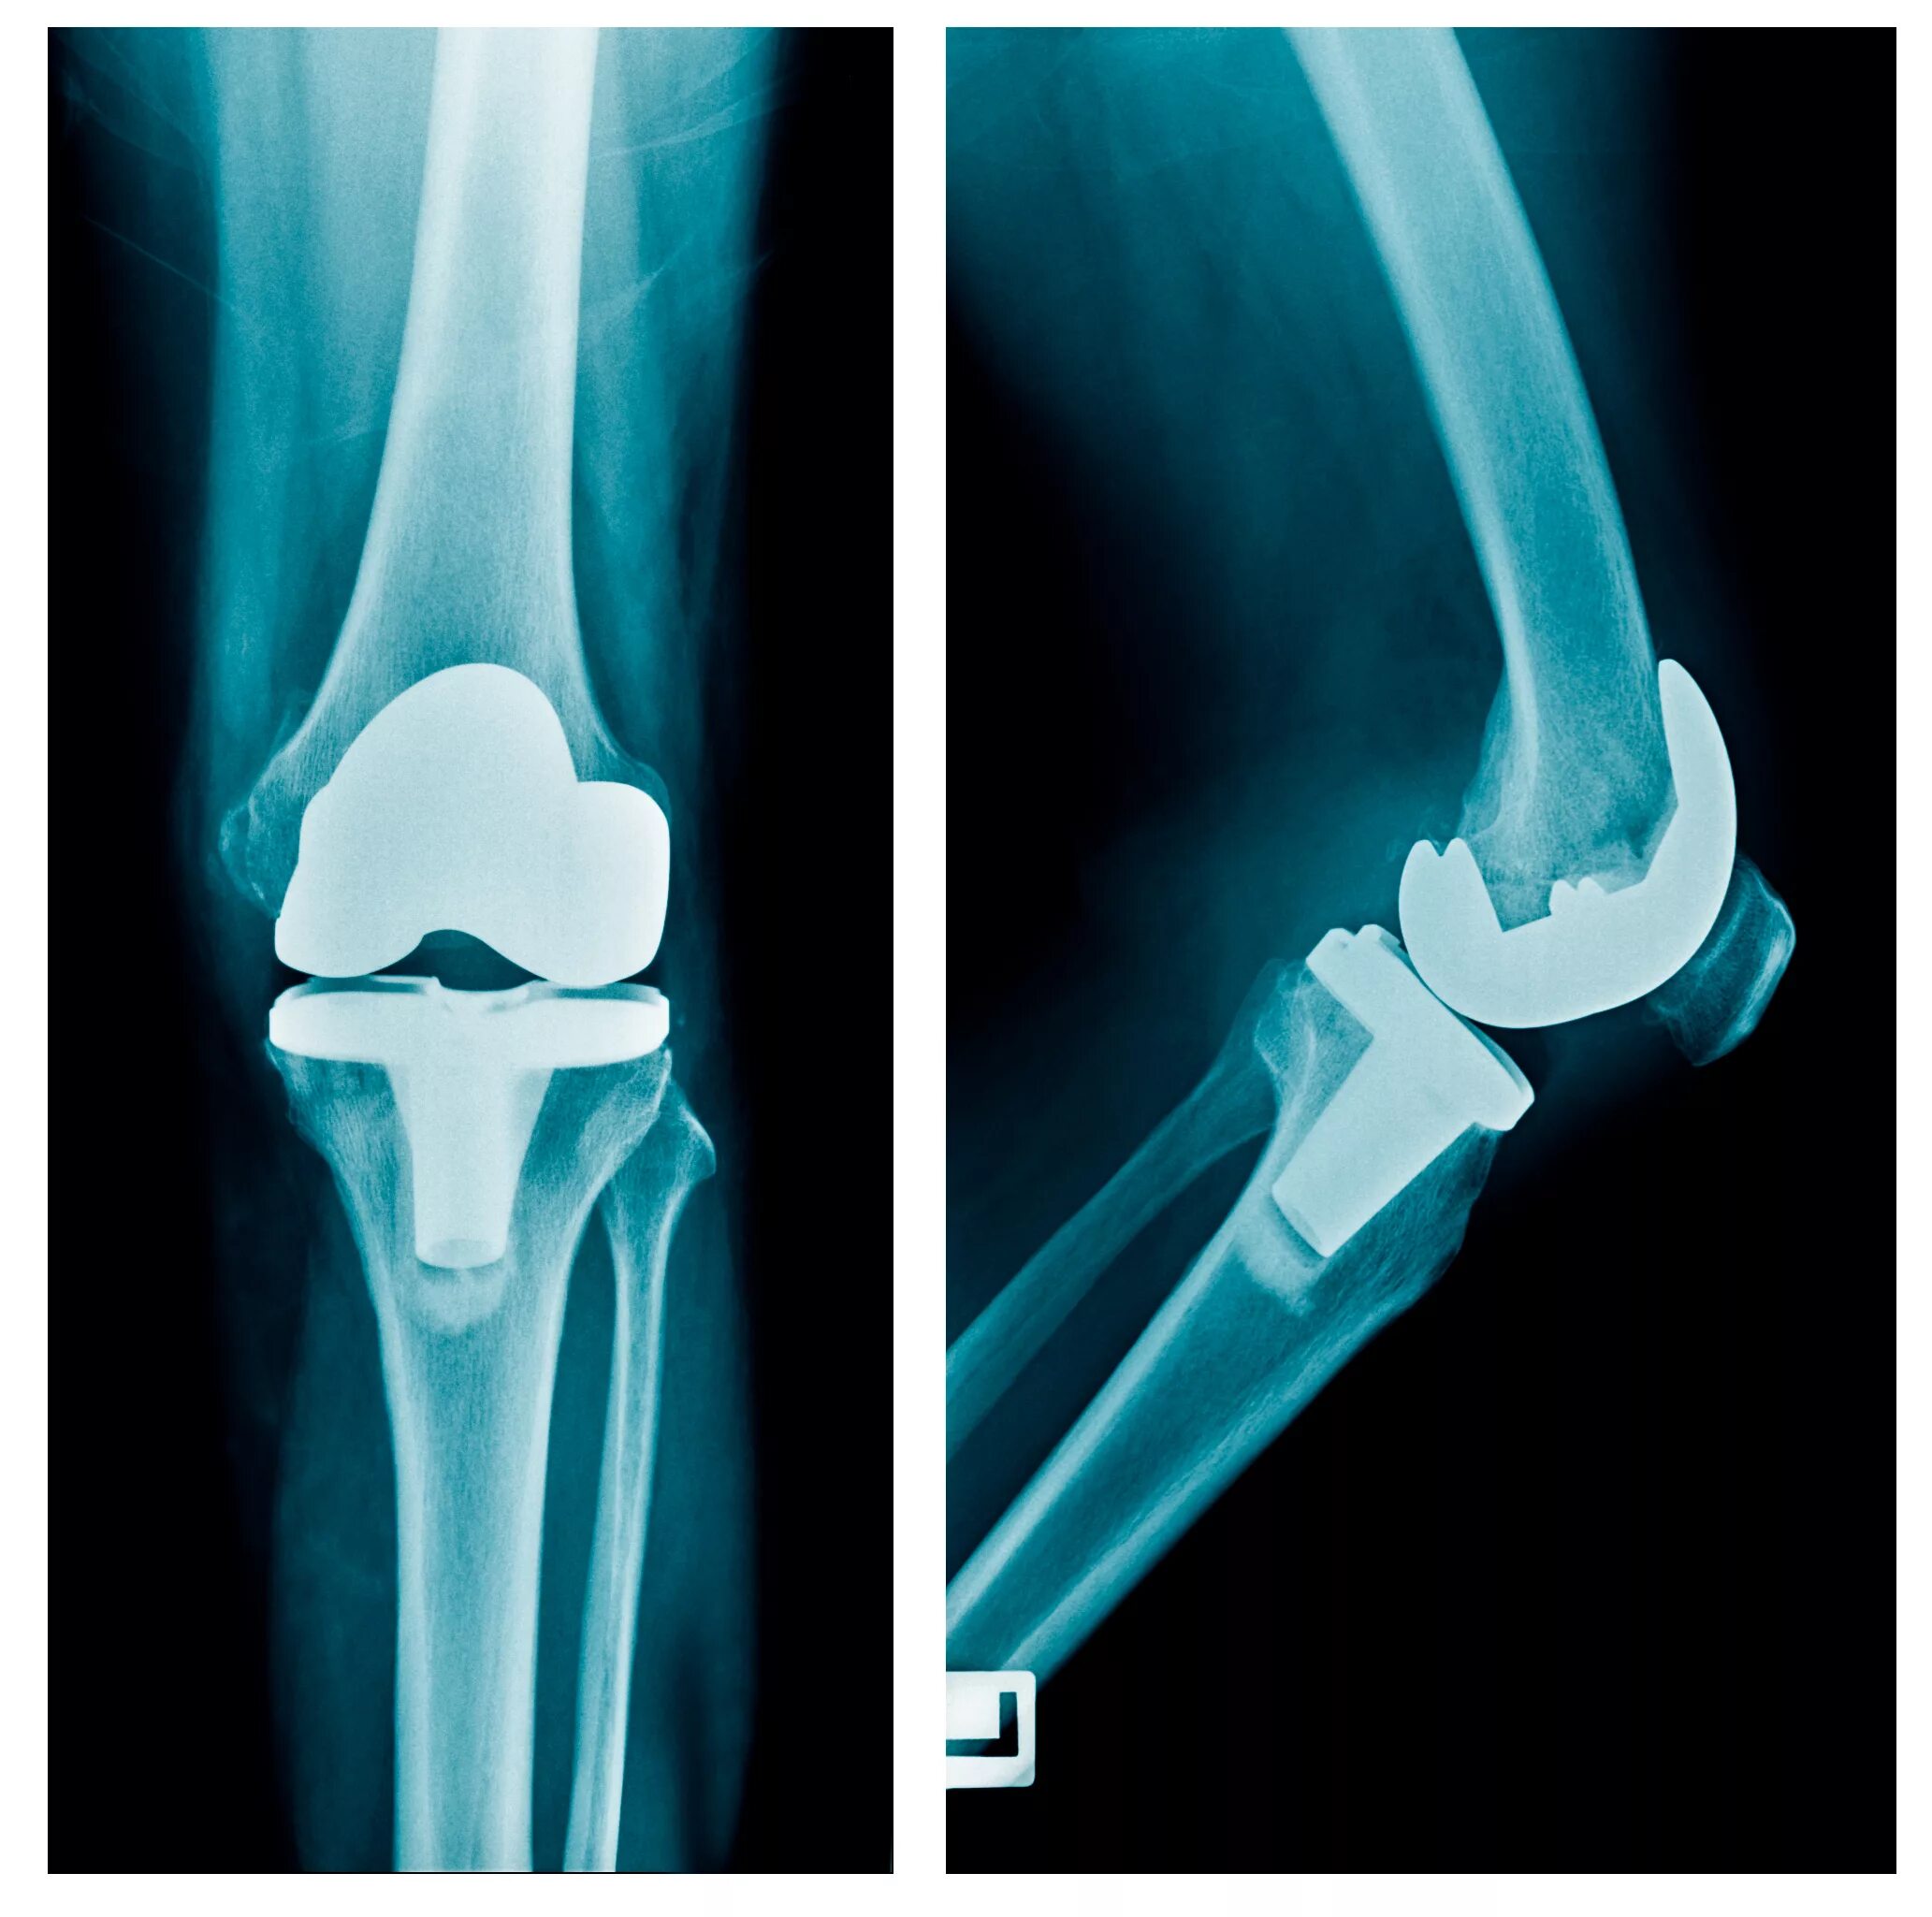

Протезы суставов отзывы